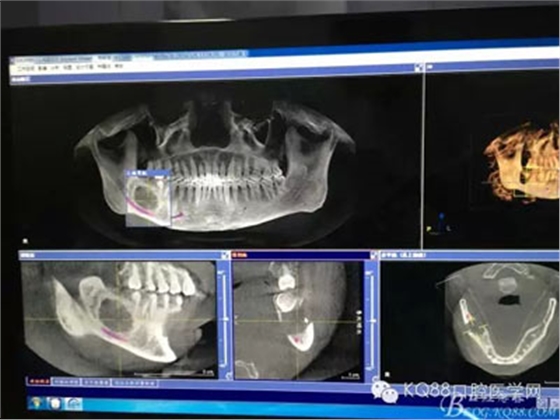

圖2.術(shù)前的CBCT檢查:48下方頜骨橢圓形囊性陰影,下方接近下頜管。

圖3.這張重建的全景片,似乎48就漂浮在囊腔上方,由此感覺(jué)48拔除如同探囊取物一般。

圖4.三維重建也提示:48拔除難度不大